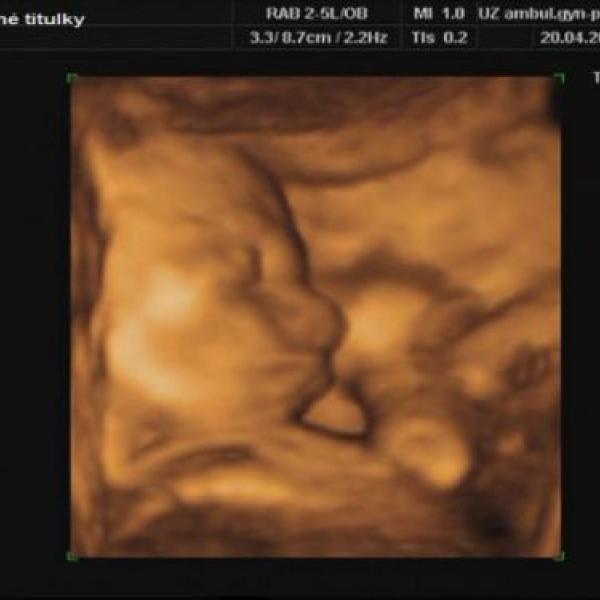

Ráda se kochám fotečkami z přípravy na miminko a vašich ratolestí a všeho možného, takže jsem se rozhodla také se pochlubit. Časem přidám i fotečky bříšenka a mé maličkosti.